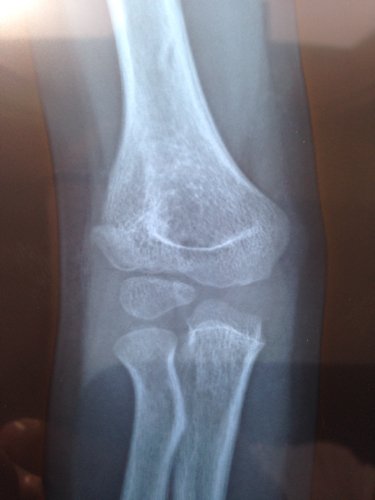

孩子5周岁 右肱骨外髁骨折  ,右尺骨鹰嘴骨折 医生给接骨 归位 石膏固定 ,一个月后拆了石膏 ,孩子胳膊伸不直 ,拆石膏的第二天发现患肢 处 有点黑青 和肿,这是怎么回事 图片是拆完石膏拍的